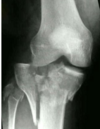

abnormalities

right posterior elbow dislocation displace fracture radial head